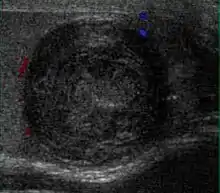

Embryonal cell carcinomas, a more aggressive tumor than seminoma usually occurs in men in their 30s. Although it is the second most common testicular tumor after seminoma, pure embryonal cell carcinoma is rare and constitutes only about 3 percent of the nonseminomatous germ cell tumors. Most of the cases occur in combination with other cell types. At ultrasound, embryonal cell carcinomas are predominantly hypoechoic lesions with ill-defined margins and an inhomogeneous echotexture. Echogenic foci due to hemorrhage, calcification, or fibrosis are commonly seen. Twenty percent of embryonal cell carcinomas have cystic components. The tumor may invade into the tunica albuginea resulting in contour distortion of the testis [Fig. 4].